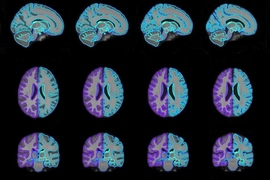

Brain temperature and free water increases after mild COVID-19 infection

Brain volume measured by synthetic magnetic resonance imaging in adult moyamoya disease correlates with cerebral blood flow and brain function

Microstructural brain abnormalities, fatigue, and cognitive dysfunction after mild COVID-19